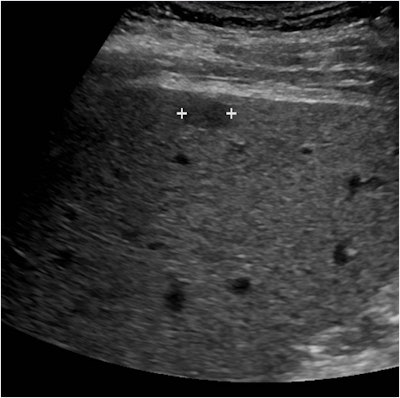

Above, small superficial hypoechoic mass (marked by calipers) in the cirrhotic liver of a 64-year-old man. Below, at 17 seconds after contrast injection, the mass is hypervascular relative to the remainder of the liver and appears brighter on this image. All images courtesy of Dr. Stephanie Wilson.